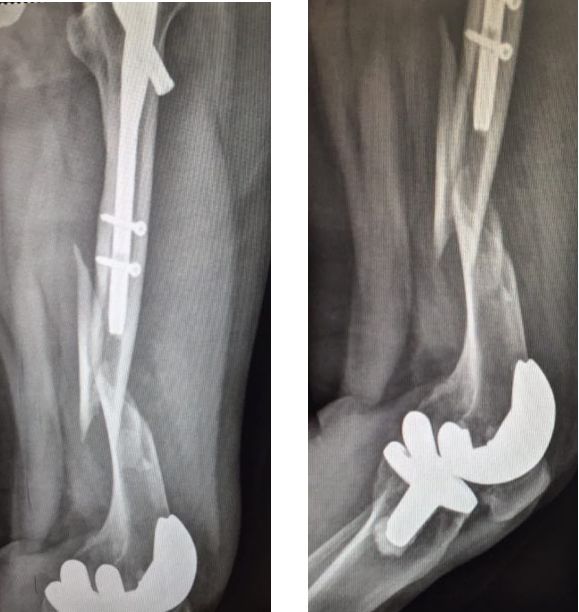

补救:取下一枚钉子骨折愈合了,关键是取钉子后减少了应力集中,延长了钢板的寿命,骨折愈合了。如果骨不愈合钢板迟早断裂(钢板当初放在内侧会好,蝶形骨块不会坏死,腓骨固定后外侧稳定,内外柱均衡愈合机会增加,当然最好还是髓内钉)。

取下3枚钉子骨折愈合了,与上一例同一位医生所做。张力带钢板,去除3螺钉后,钢板的应力分散,弹性增加,骨折端承受有效的应力刺激,最后骨折愈合。去除螺钉的时候如果加骨皮质剥离重新激发骨愈合会更好。(最好选髓内钉)